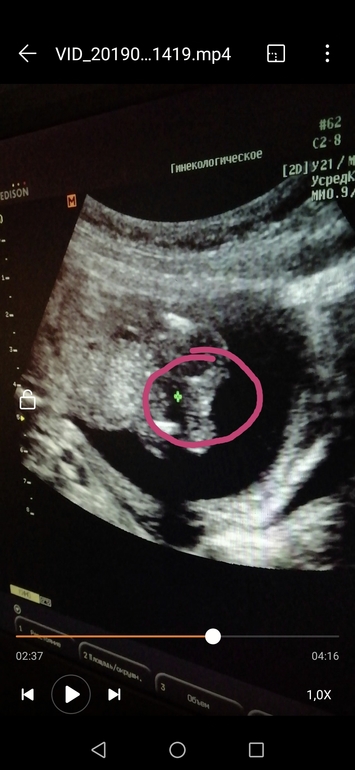

Вопросы про УЗИ, обследования и анализы: что, где, как, когда?На узи сказали что точно мужчинка)))

Но вот интересно, у кого ещё были фото с такого ракурса? Снизу?) тоже так торчал?)) второе фото) 14 неделя)

Я вот тоже засомневалась, что прям так ярко) но узкистка говорит 100% парень